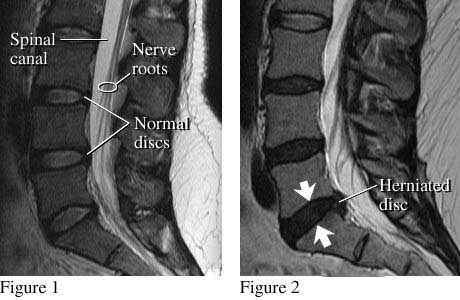

Cum arată pe radiografie hernia de disc?

Pentru a înţelege mai bine procesul de herniere a unui disc intervertebral, vom folosi imaginea alăturată. În figura din stânga putem observa cum arată la radiografie o coloană vertebrală normală. Discurile sunt la locul lor, fără a afecta canalul spinal (cel prin care trec rădăcinile nervoase). În cea de-a doua figură, în locul indicat cu săgeţi, putem observa aspectul unui disc herniat. Acesta presează canalul spinal, afectând nervii. Unii dintre aceşti nervi corespund musculaturii picioarelor. Aceasta este explicaţia coborârii durerii pe picioare în cazul herniilor de disc. Prin operaţie, neurochirurgul urmăreşte să extragă acea porţiune de disc herniat care aplică presiune pe nervi.